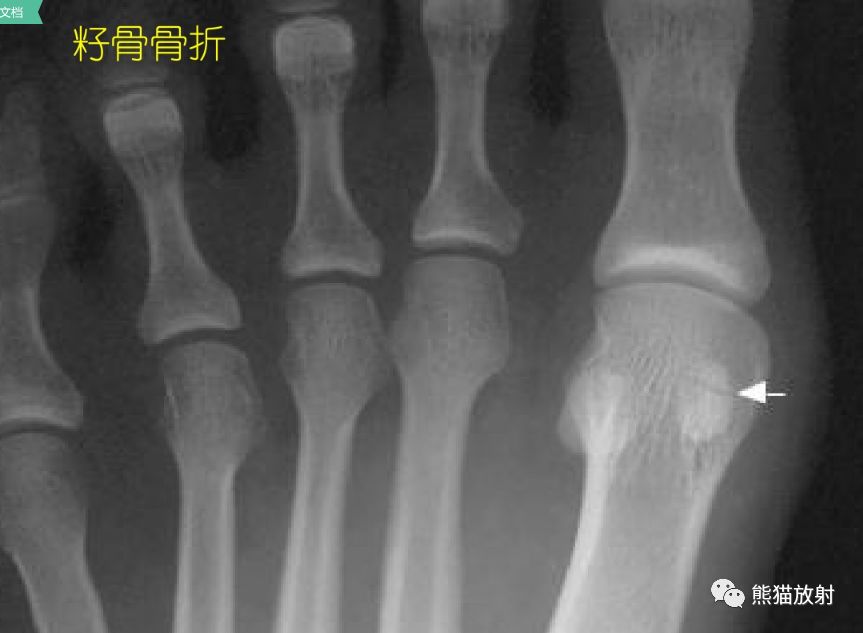

032期 】2016-01-19 . 籽骨、副骨、永存性骨骺

籽骨、副骨及永存骨骺,请别再误诊!_搜狐其它